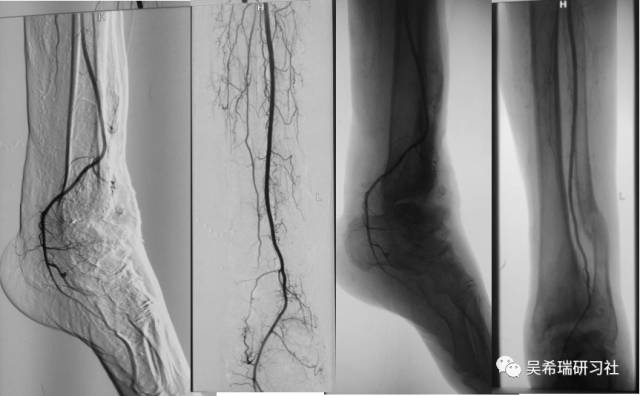

电击伤80天无知名动脉僵硬性足下垂大段骨坏死

TIPS:双段骨搬移技术 + 开放植骨表面鳞片式骨水泥多重胫跖骨牵引技术外固定架吴氏构型(单边+半环搬移)